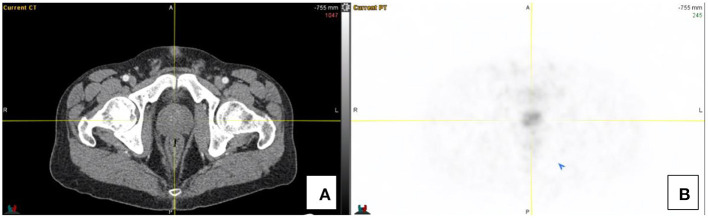

三十多年来,Indium 111 DTPA Octreotide(Octreoscan)一直是核医学生长抑素受体(SSTR)成像的支柱。PET/CT的出现带来了生长抑素的新类似物,由于其标记用于正电子成像的镓68,因此具有更高的亲和力和改进的分辨率。最常用的类似物包括DOTATATE、DOTATOC和DOTANOC。然而,镓68–1,4,7,10-四氮杂环十二烷-1,4,7,10-四乙酸(DOTA)-奥曲酸(DOTATE)可能是最常见的非FDG(氟-2-脱氧葡萄糖)PET示踪剂,与PSMA(前列腺特异性膜抗原)并列。与F18标记的FDG相比,由于Ga68发生器的可用性,它不需要接近回旋加速器。DOTATATE是一种生长抑素类似物,可以对细胞表面的生长抑素受体进行全身成像。68Ga-DOTA化合物为高分化(1级和低2级)神经内分泌肿瘤(NETs)提供了成像标准,并用于NETs患者的分期、表征和再分期。68Ga-DOTATE与18F-FDG具有互补作用,其中肿瘤可能表现出不同程度的分化。此外,它还可作为治疗的前奏,用于选择使用治疗方法进行肽受体放射性核素治疗的患者。对放射性示踪剂的正常生物分布有充分的了解,对于最佳的患者结果和避免潜在的假阳性(如炎症、正常的胰腺钩突摄取和成骨细胞活性)至关重要。在这篇综述中,我们将在图像的支持下描述68Ga-DOTATE的正常外观和潜在的陷阱,以帮助改进对这一关键创新工具的解释,从而管理表达SSTR的肿瘤个体。

Indium 111 DTPA Octreotide (Octreoscan) has been the pillar of Somatostatin receptor (SSTRs) imaging in nuclear medicine for over three decades. The advent of PET/CT brought new analogs of somatostatin that have higher affinity and improved resolution due to their labeling to Gallium 68 for positron imaging. The most used analogs include DOTATATE, DOTATOC and DOTANOC. However, Gallium 68-1,4,7,10-tetraazacyclododecane-1,4,7,10-tetraacetic acid (DOTA)-octreotate (DOTATATE) is probably the most common non-FDG (fluoro-2-deoxy glucose) PET tracer alongside PSMA (prostate specific membrane antigen). In contrast to F18-labeled FDG, it does not require proximity to a cyclotron due to the availability of the Ga68 generator. DOTATATE is a somatostatin analog which allows whole body imaging of somatostatin receptors on cell surfaces. 68Ga-DOTA compounds provide the imaging standard for well-differentiated (Grade 1 and low grade 2) neuro-endocrine tumors (NETs) and is utilized in the staging and characterization and restaging of patients with NETs. 68Ga DOTATATE has a complementary role with 18F-FDG where tumors may exhibit varying degrees of differentiation. It furthermore has application as a prelude to therapy in selecting patients for peptide receptor radionuclide therapy using a theranostic approach. A sound knowledge of the normal biodistribution of the radiotracer is imperative for optimal patient outcome and to avoid potential false positives such as inflammation, normal pancreatic uncinate process uptake and osteoblastic activity. In this review, we will describe the normal appearances of the 68Ga DOTATATE and the potential pitfalls with the support of images to aid in improving interpretation of this crucial innovative tool in the management of individuals with tumors expressing SSTRs.